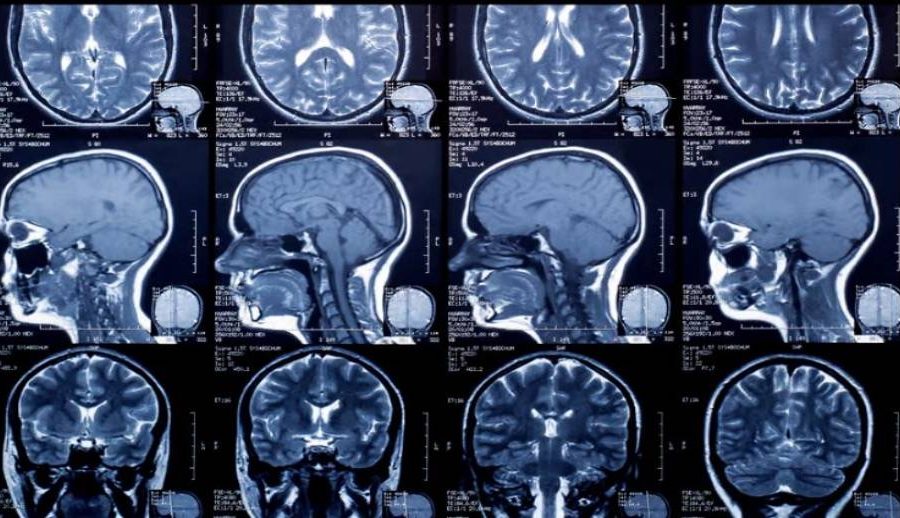

मन्त्री पौडेलले बुधबार मन्त्रीस्तरीय निर्णय गर्दै फिल्ममा हुने खर्च कटाएर एक्सरे, एमआरआई तथा सिटी स्क्यानको शुल्कसमेत घटाउने निर्णय गरेका हुन्। मन्त्री प्रदीप पौडेल कटौती गर्दै नागरिकलाई राहत दिने गरी यस्तो निर्णय गरिएको बताए।

मन्त्रालयका प्रवक्ता डा. प्रकाश बुढाथोकीले स्वास्थ्य मन्त्रालयमातहतका २२ अस्पतालले क्रमैसँग नागरिकलाई डिजिटल रिपोर्ट उपलब्ध गराउने जानकारी दिए। उनले स्वास्थ्यका लागि हानिकारक मानिने एक्सरे निर्णय हाल संघीय अस्पतालमा लागू गरिने फिल्मको प्रयोगमा भइरहेको ठूलो धनराशी खर्च र क्रमैसँग निजी तथा अन्य तहगत अस्पतालमा एक्सरे, एमआरआई तथा सिटी स्क्यानको शुल्क घटाइने समेत विस्तार गर्ने मन्त्रालयको योजना छ।

हाल वीर अस्पतालले वर्षमा करिब चार करोड रुपैयाँ रेडियोलोजी फिल्मका लागि खर्च गर्ने गरेको तथ्याङ्क छ। यसै गरी कान्ति बाल अस्पतालमा करिब तीन करोड खर्च हुने गरेको छ। यो निर्णयले सक्नीय अस्पतालको वार्षिक करिब ५० करोड बजेट बचत हुने अनुमान गरिएको छ।

प्रवक्ता डा. बुढाथोकीले निजी र देशभर डिजिटल रिपोर्ट दिन सकिए वर्षमा करिब एक अर्ब रुपैयाँ रकम बिदेसिनबाट रोकिने जानकारी दिए। उनले मन्त्रालयको यो निर्णयले नागरिकलाई रेडियोलोजी सेवामा लागतसमेत कम पर्ने र स्वास्थ्यमा समेत नकारात्मक प्रभाव कम पर्ने बताए।